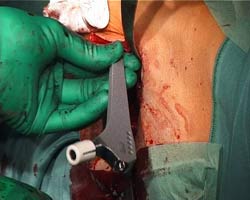

Abb. 10

Der

Schaft wird zuerst händisch eingebracht und anschließend

mit einem Kunststoffeinschläger in die definitive

Position eingeschlagen. |

|